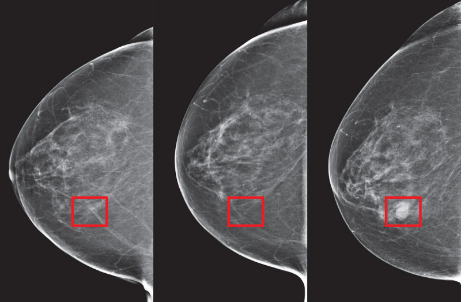

Cancerul de sân este cea mai frecventă formă de cancer la femei și a doua cauză a deceselor provocate de tumorile maligne, după cancerul de plămân, în populația feminină. Boala se declanșează atunci când unele celule din structura glandei mamare capătă unele mutatii la nivel genetic și se înmulțesc incontrolabil, formând o tumore.

Diagnostic

Examenul clinic al sânului și al ganglionilor limfatici din axila, precum și testele imagistice orientează diagnosticul asupra unei tumori de sân și a gradului de extindere locală.

Cele mai performante metode de diagnostic a cancerului mamar le puteți găsi practice în fiecare spital din Turcia. Acest fapt este datorat domeniului nou SANATATEA SÂNILOR!

Femeile cu vârsta de peste 40 ani sunt cele mai predispuse apariției cancerului mamar. Tehnologiile și metodele performante din clinicele Turcești ajută nu doar la depistarea cu înaltă precizie a tumorilor țesutului mamar, ci și la tratarea eficientă a lor. Unele dintre metodele și aparatele moderne folosite sunt:

- Ultrasonografia 4D, ce ajută la depistarea precoce a cancerului cu o acuratețe apropiată de 100%

- Tomosinteza

- Biopsia stereostatică și asistată

- Echipamentul MAMMOMAT Revelation, ce asigură acuratețea diagnosticului prin efectuarea tomografiei cu un unghi de 50°, astfel echipamentul mamografic atinge cea mai mare rezoluție de adâncime prin tehnologia unică de Tomosinteză mamară HD 50°.